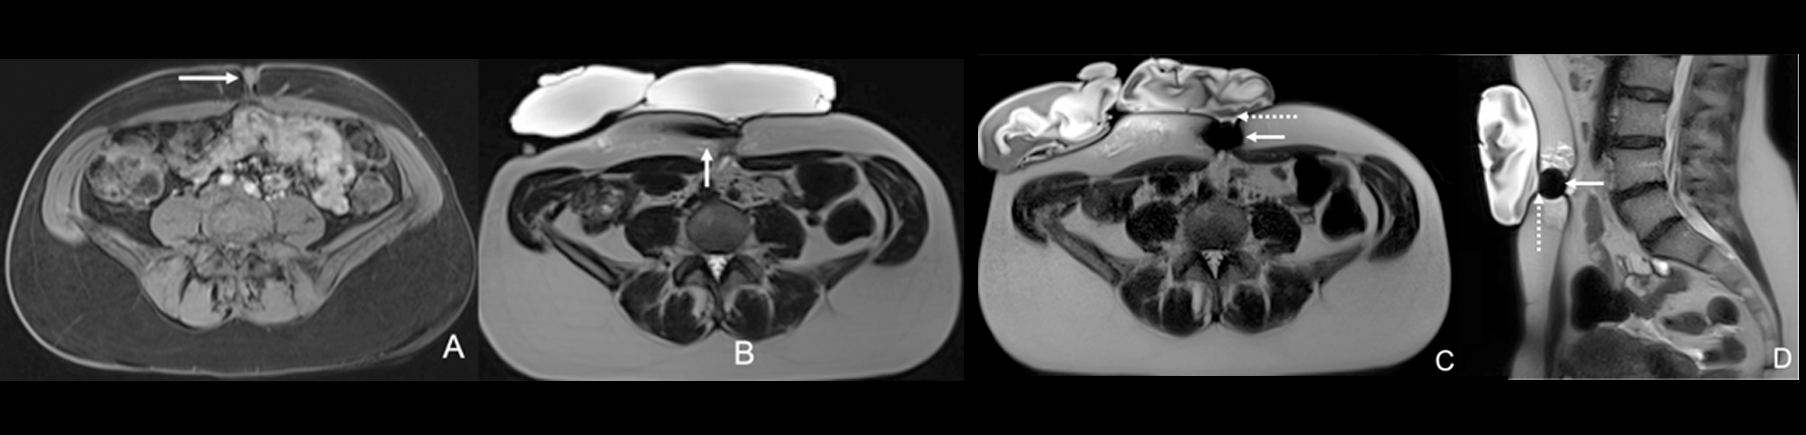

Based on these encouraging premises, interventionalists have recently started to push the boundaries by treating painful endometriosis deposits which are outside the abdominal wall and/or are located in challenging and unusual anatomic sites (i.e. umbilicus, inguinal canal, diaphragm, etc.) (Fig. 2). A recently published retrospective case-series showed that cryoablation is safe and effective when proposed in these challenging/unusual locations with reported rates of primary/secondary complete pain relief and adverse events respectively at 86.7%, 93.3% and 12.5%.